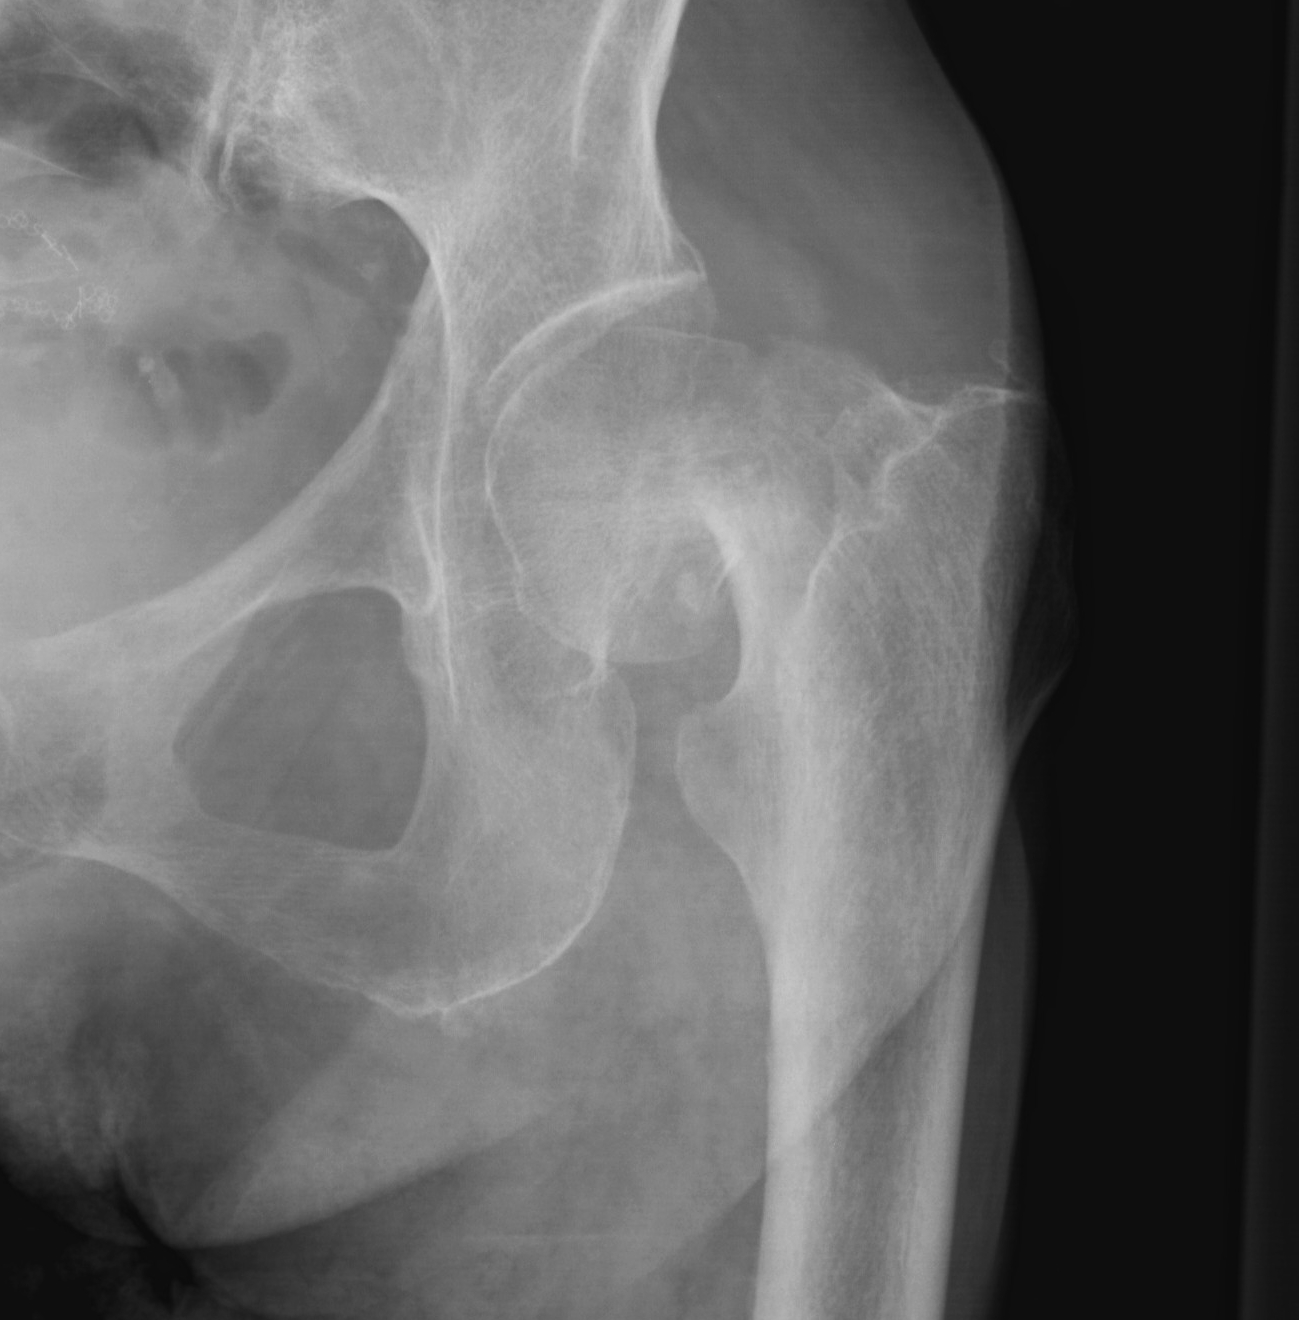

Fracture distal to articular surface & proximal to intertrochanteric region

On average 4 years younger than intertrochanteric fracture

One year mortality as high as 36%

Only 1/3 will return to pre-fracture living environment